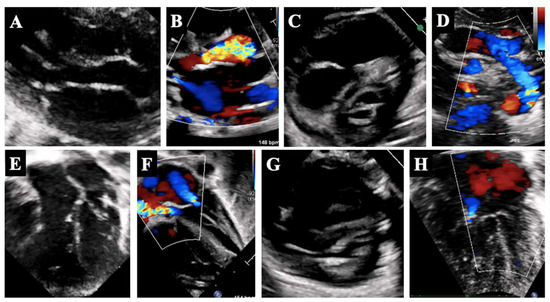

4. Borderline Right Ventricle: Predictors of Biventricular Repair

- The determination of whether the RV can support (or can be rehabilitated to support) a full pulmonary circulation and the systemic venous return;

- The morphologic assessment of the RV (unipartite, bipartite, or tripartite) and the infundibulum (membranous vs. muscular pulmonary atresia);

- The assessment of the TV size, morphology, and function;

5.2. Borderline Right Ventricle